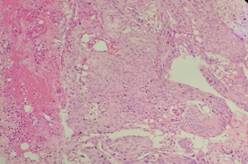

经家属同意后,医生决定栓塞肿瘤近端的供血动脉,并于当天行左侧中颅窝占位病变切除术;术中可见肿瘤灰红色,有假包膜,分块切除肿瘤;由于术前行介入栓塞,术中可见血供明显减少,且出血少,左侧大脑中动脉及左侧大脑前动脉被肿瘤压迫移位,医生给予保护后将肿瘤全切除。术后黄女士恢复顺利,已痊愈出院。病理结果显示:脑膜瘤,合体细胞型,WHO I级。

术后病理:“左侧蝶骨嵴”脑膜瘤,合体细胞型,WHO Ⅰ级